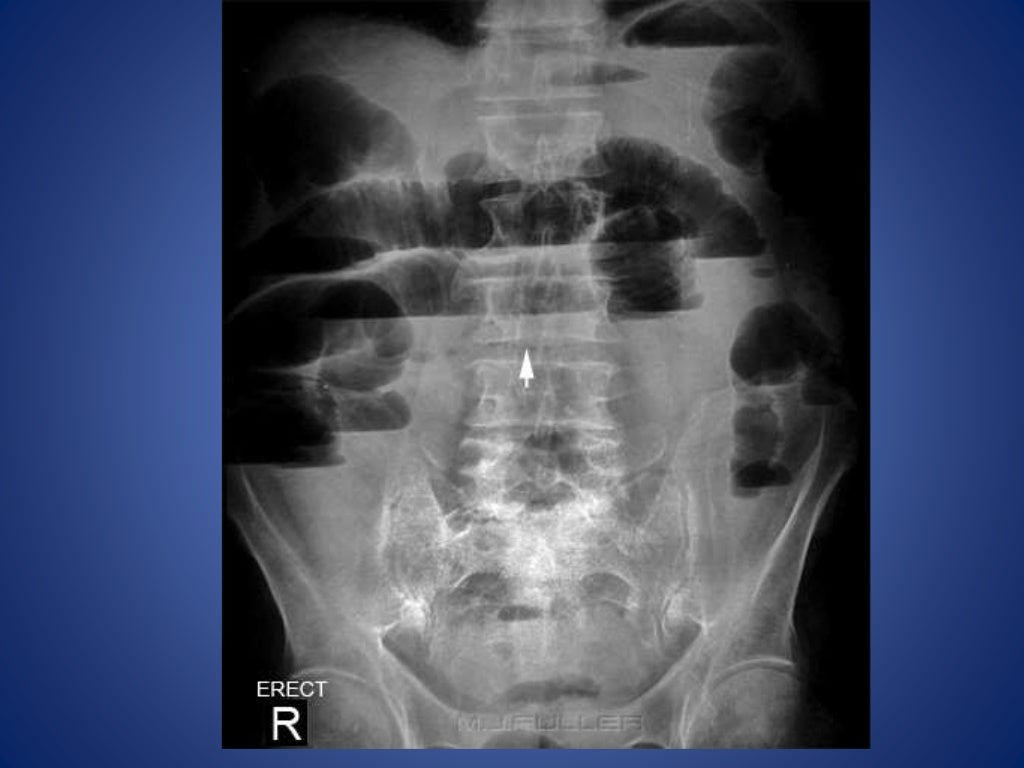

Prolonged ileus. The paralytic ileus was due to pelvic trauma and Mechanical Ileus Vs Paralytic Ileus The pathologic effects of acute intestinal obstruction are fluid and electrolyte imbalances, and mechanical consequences of increased luminal pressure on. In the pathophysiology of ileus, both types lead to the. Paralytic ileus is a severe form of ileus that occurs when peristalsis has been significantly reduced or stopped, leading to a buildup of stomach contents in. Paralytic ileus is a. Mechanical Ileus Vs Paralytic Ileus.